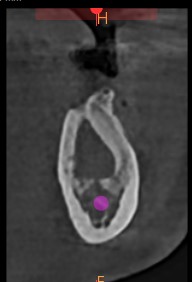

Paciente femenino de 43 años procede a la realización de una Cone Bean indicado por su odontólogo que visualizo en un estudio anterior una imagen radiopaca y radiolúcida en zona de Pd 36-37-38.  (Imagen 1 y 2). En la Vista sagital (Imagen 3) se observa imagen de contenido hipodenso, rodeado de un halo hiperdenso en zona de ausencia de pd 36, la misma se ve en corte axial (Imagen 4), por sus caracteristicas diagnóstico presuntivo de Quiste residual.  Ademas s eobserva zona hiperdensa por debajo de ápices de pd 37 y 38, la misma es de bordes nitidos y bien definidos, la pd 37 presenta un gran desgaste por lo que nos hace pensar en una desgaste por fuerzas masticatorias, por lo que el diagnostico presuntivo corresponde a una osteoesclerosis idiopática  (Imagen 1 y  5).  En las imágenes 3D no se observan alteraciones u abombamientos    (Imagen 6 y 7).

El Quiste Residual, que es la permanencia de lo que fue en algun momento un quiste radicular, radiográficamente se presenta como una imagen radiolúcida bien definida en zona edéntula, con cortical fina o gruesa, que puede estar o no relacionada con el tejido alveolar de un diente extraído o adyacente al reborde alveolar presentando una imagen o patrón en “copa de coñac” esto suele indicar la presencia de una lesión intraósea que se extiende a los tejidos blandos. Sin embargo, se han reportado casos de quistes residuales de larga data con presencia de calcificaciones intrínsecas, siendo una característica rara. Ademes suele afectar con mayor frecuencia a la maxila que la mandíbula. Al tratarse de una imágen única, redondeada u ovalada con presencia de cortical, el Quiste Residual suele confundirse con un Ameloblastoma Uniquístico, en estadio inicial, Queratoquiste Odontogénico o un Quiste Óseo Simple. Cabe recordar que todas estas entidades pueden expandir discretamente las tablas óseas como el Quiste Residual, pero es la anamnesis la que orienta hacia el diagnóstico correcto.